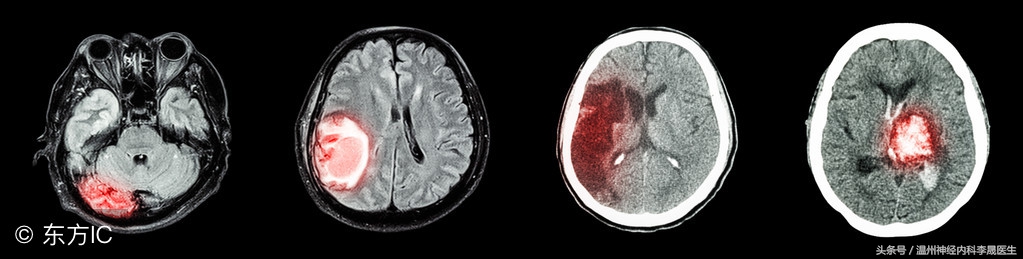

1)CT 首选

血肿为圆形/卵圆形、边界清楚的高密度灶。可确定直径0.5cm以上血肿的部位、大小、形态、有否破入脑室、血肿周围水肿带和占位效应。动态观察可发现进展型出血。有助于指导治疗和判断预后。

脑出血灶有两型:

1 稳定型:血肿形态规则,密度均一

2 活动型:形态不规则,密度不均

2)MRI

对脑出血敏感,可明确出血部位、范围,脑水肿及脑室情况。

MRI的表现取决于血肿所含血红蛋白量的变化。

对幕下出血优于CT,可发现CT不能确定的(脑干或小脑)小量出血,能分辨病程1个月后CT不能辨认的脑出血(区别陈旧性出血和梗死),显示血管畸形流空现象。

可根据血肿信号(Hb)的动态变化判断出血时间。

脑干出血MRI表现